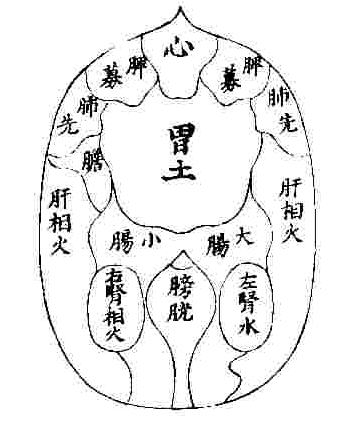

| HOME > 学習ノート> >お腹のみかた、触れ方② 腹診は先人たちのご苦労されて残されたものから、多くを学ぶことができます。 たにぐち書店の難経からお腹の経絡図をお借りして載せています。 ツボも細かく書かれていますが、お腹にはすべての経絡が関わっています。 肺経は経絡図を見ますと、表面上では胸部の一部と腕だけだと思われますが、決してそうではなく腹部の中に 入って働いていることが右の図をご覧頂くとお判り頂けるかと存じます。   また、お腹のみかたも、鍼道秘訣集、夢分の描かれたものや増永静人先生の腹部スジ反応部位をご覧頂くと、 人により観方、感じ方が異なっていることが分かるかと思います。 ではどちらを信じて学べば良いのでしょうか。 どちらの方もこの道の大家でいらっしゃいますから迷うでしょう。 答えですが、まず、どちらも覚え、頭の片隅に入れておきますが、最終的には幾度も施術をしながら自分の感覚 を信じ、答えを出すことです。 鍼道秘訣集 夢分